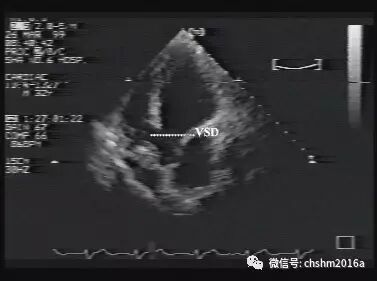

图2.3.4   室间隔连续中断明显

VSD:室间隔缺损 RV:右室 RA:右房 LA:左房